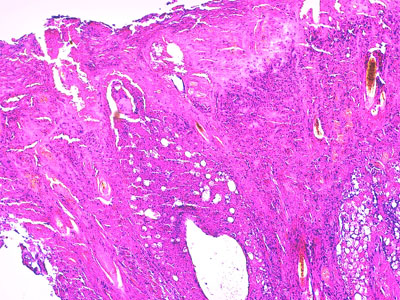

- l’examen histopathologique de deux biopsies cutanées (Photos 12 et 13) confirme l’existence d’une sévère dermatite nécrosante et ulcérative, avec lésions secondaires de pyodermite profonde, associées à une nécrose des annexes pilo-glandulaires. En dépit de l’absence de corps d’inclusion viraux nettement objectivables en position intra-nucléaire, l’aspect histopathologique est fortement évocateur d’une virose cutanée.

Photo 12 : Examen histopathologique de biopsies cutanées (LAPVSO)